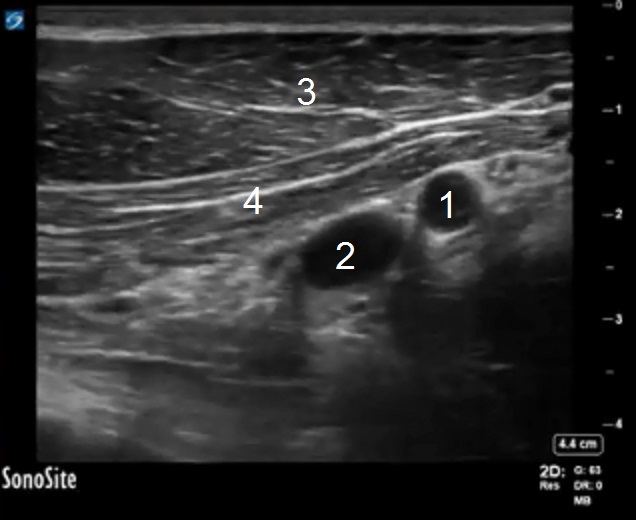

PECS Anatomy 1 Image

Axillary Artery

Axillary Vein

Pectoralis Major Muscle

Pectoralis Minor Muscle